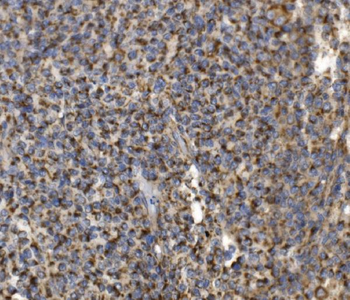

- PPM1D Rabbit Polyclonal Antibody [orb704535]Featured

IF, IHC-Fr, IHC-P

Human, Mouse, Rat

Mouse, Rat

Rabbit

Polyclonal

Unconjugated

100 μl, 50 μl, 200 μl - HSC70 Mouse Monoclonal Antibody [orb704174]Featured